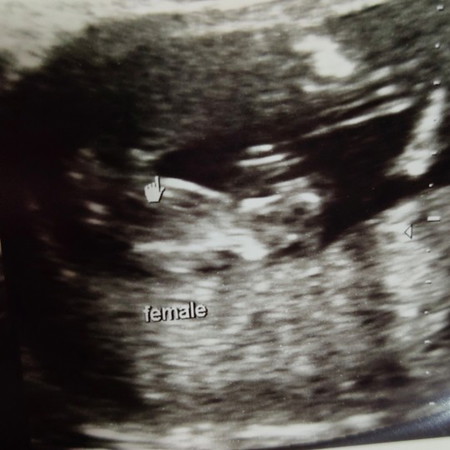

หมอบอกผู้หญิง70%แม่ช่วยดูหน่อยค่ะ อ้าขาโชว์แต่ไม่แน่ใจ

บ้านนี้หมอนับให้ดูว่ามีกลีบ3กลีบ หมอบอกว่าลูกสาว แต่แม่รู้สึกว่ากลีบใหญ่จัง คงไม่ใช่ไข่นะ แต่ยังไงก็เชื่อหมอไว้ก่อนค่ะ 😊

ถ้าน้องถ่างขาให้ดูแล้วไม่มีแหลมๆคงหญิงละคะ

ลูกสาวค่ะ. บ้านนี้ก็อลูกสาวแบบเดียวกันเลย

น่าจะผู้หญิงนะคะ เชื่อหมอค่ะ

เหมือนผู้หญิงเลยค่ะ